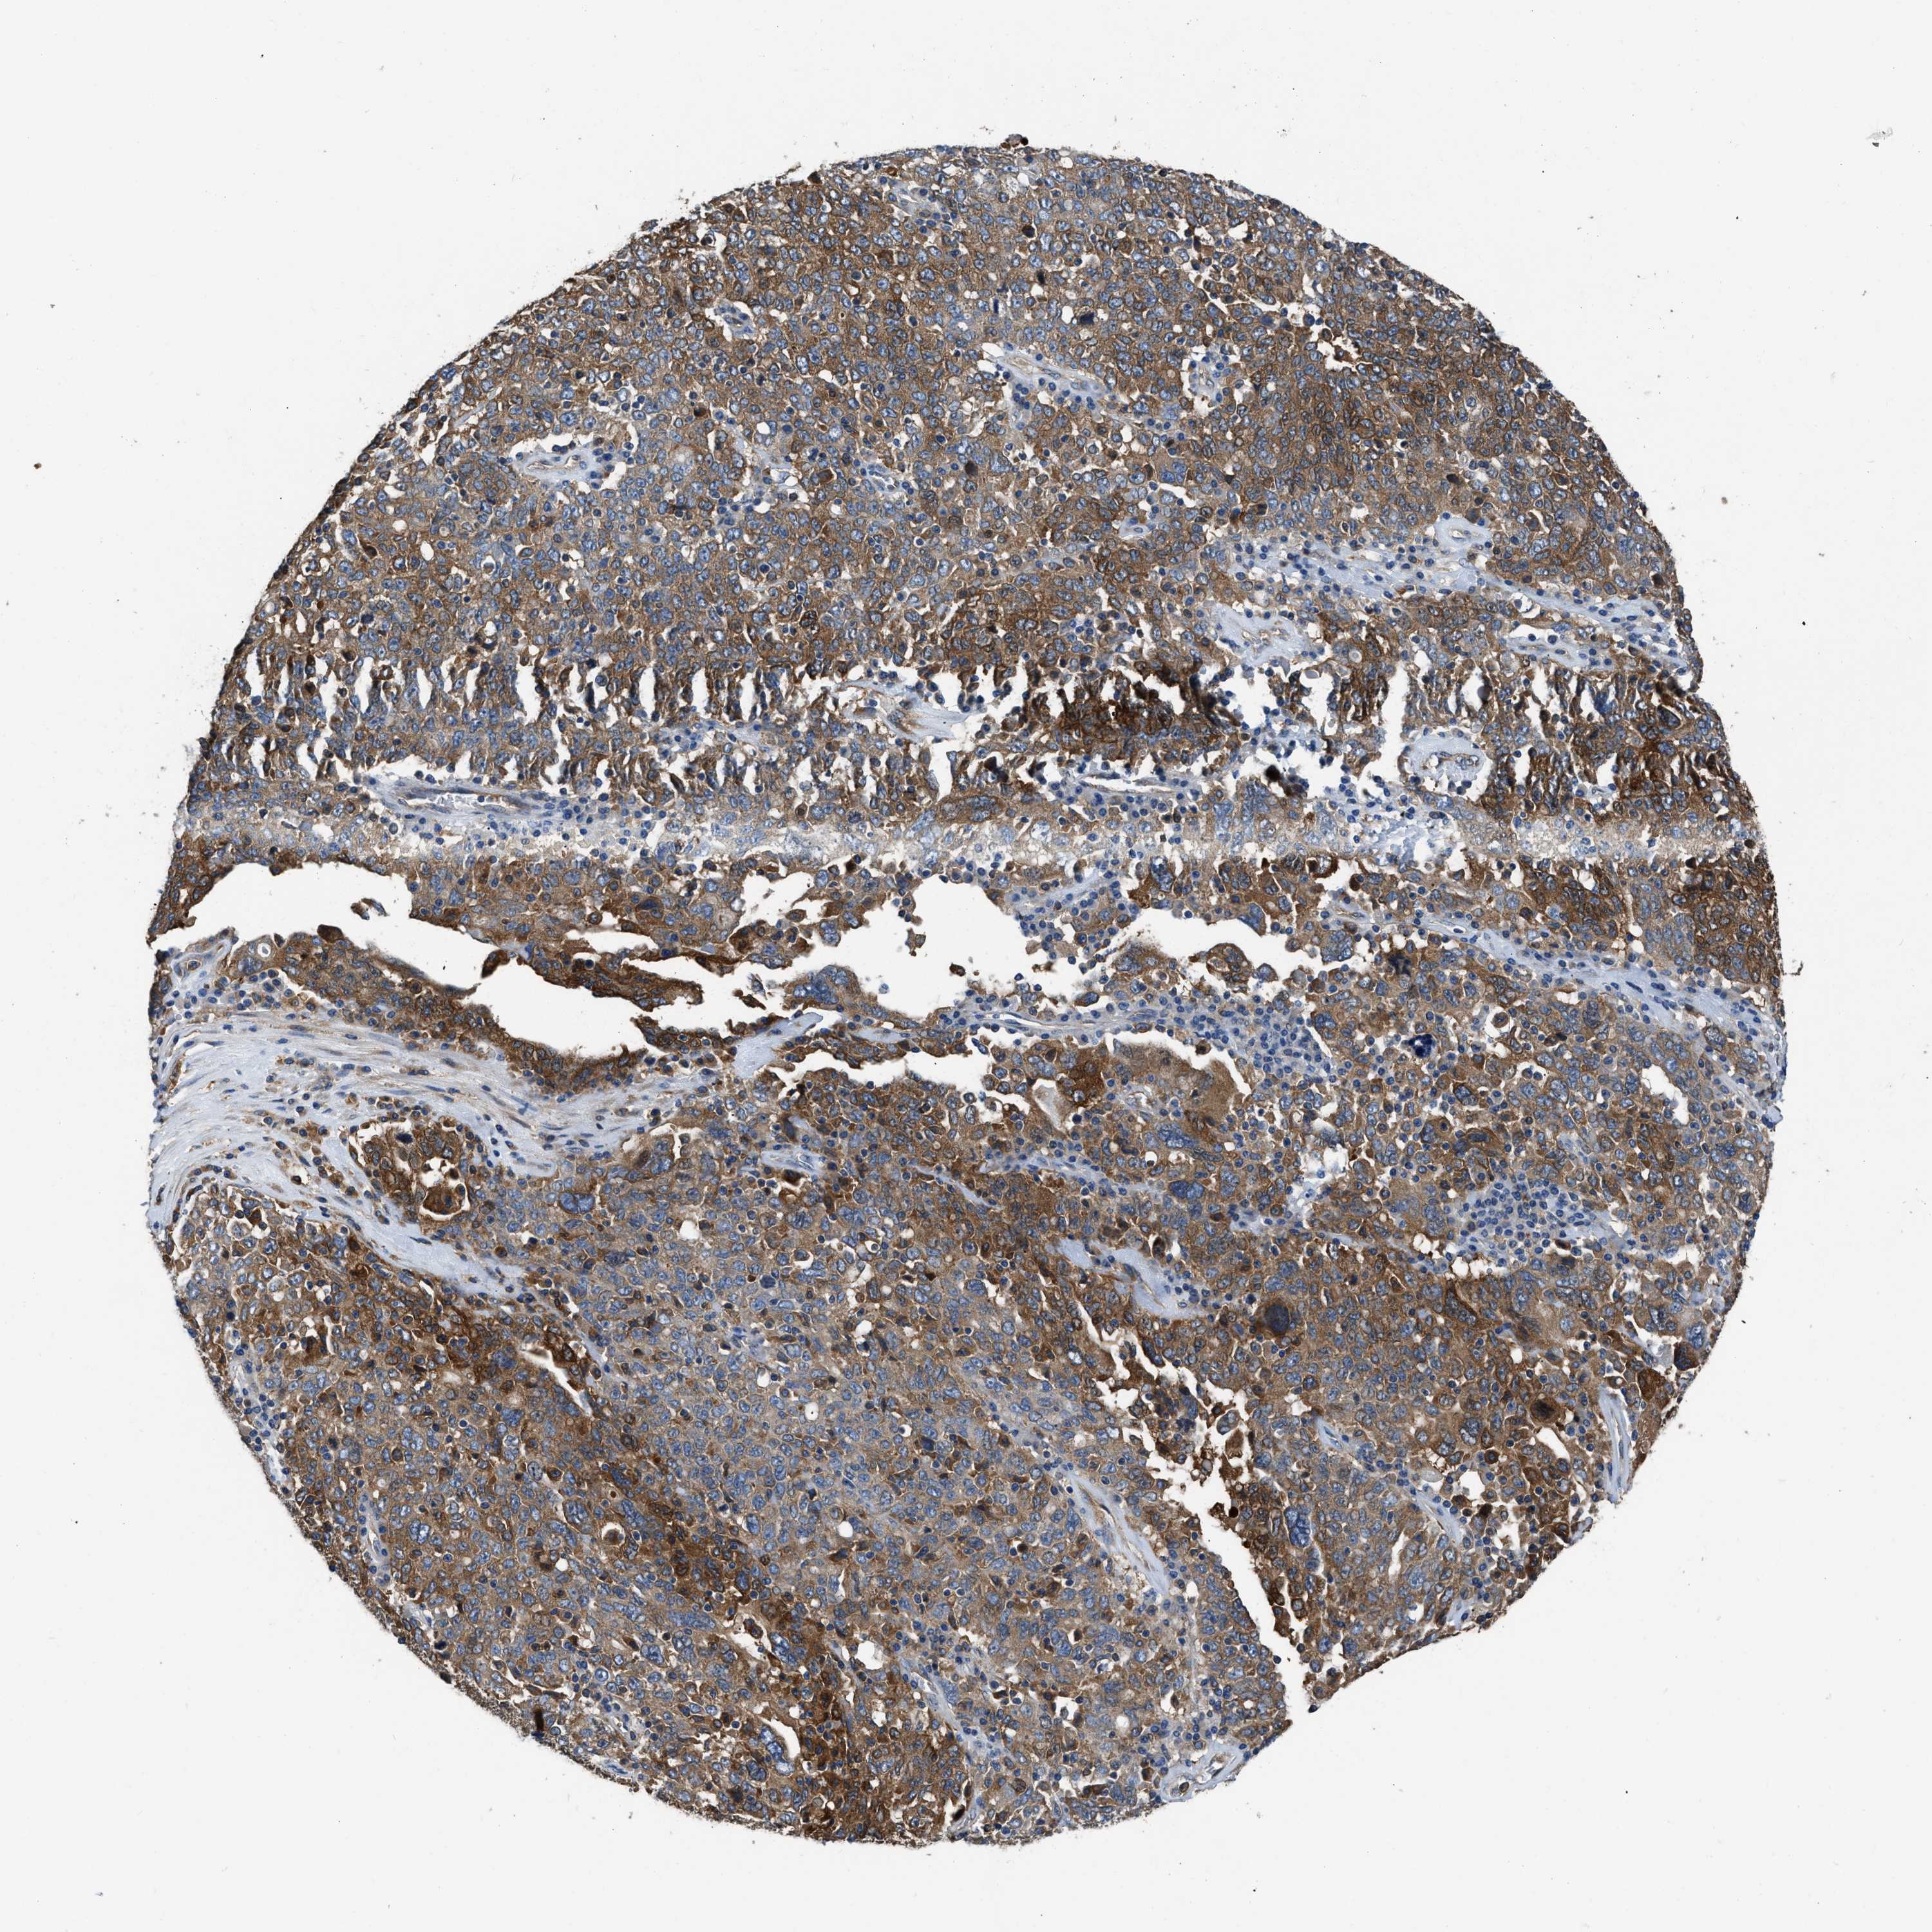

OVARIAN CANCER - Protein expressioni

A mouse-over function shows sample information and annotation data. Click on an image to view it in a full screen mode. Samples can be filtered based on level of antibody staining by selecting one or several of the following categories: high, medium, low and not detected. The assay and annotation is described here.

Note that samples used for immunohistochemistry by the Human Protein Atlas do not correspond to samples in the TCGA dataset.

Antibody stainingi

Antibody staining in the annotated cell types in the current human tissue is reported as not detected, low, medium, or high, based on conventional immunohistochemistry profiling in selected tissues. This score is based on the combination of the staining intensity and fraction of stained cells.

Each image is clickable and will lead to virtual microscopy that enables deeper exploration of all samples and also displays staining intensity scores, fraction scores and subcellular localization as well as patient and tissue information for each sample.

Antibody HPA029501

Antibody CAB019421

Staining

High

Medium

Low

Not detected

Intensity

Strong

Moderate

Weak

Negative

Quantity

>75%

75%-25%

<25%

None

Location

Nuclear

Cytoplasmic/membranous

Cytoplasmic/membranous,nuclear

Cystadenocarcinoma, serous, NOS